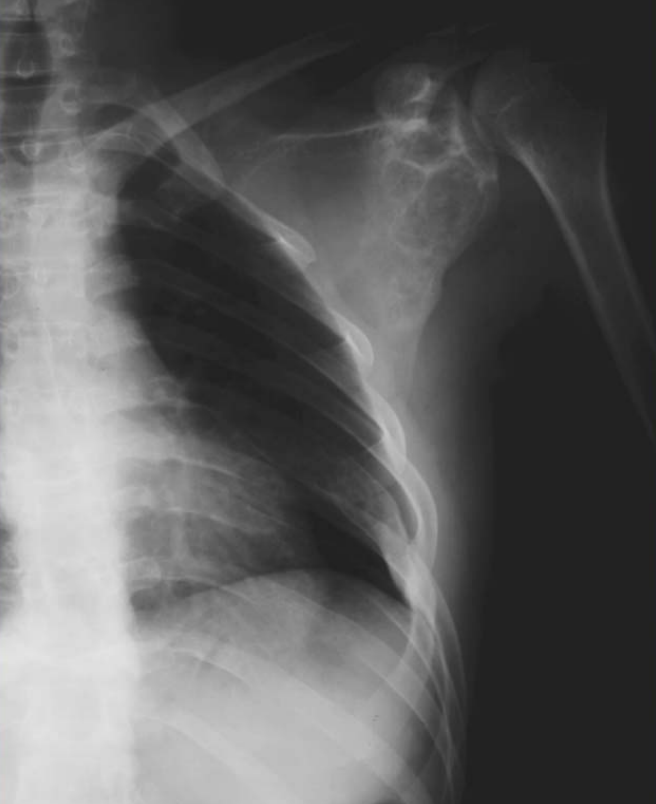

Figure2